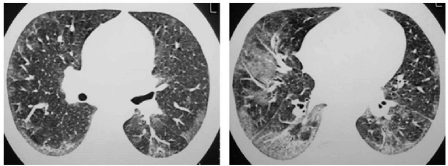

Uma paciente do sexo feminino, 33 anos, procurou pneumologista com história de dispneia progressiva há dois anos, atualmente para subir qualquer aclive; tosse seca frequente há seis meses. Tabagista ativa desde os quatorze anos de idade (carga tabagística: 35 maços-ano). Negava asma e exposições ambientais ou ocupacionais relevantes. Bancária desde os 23 anos de idade, trabalhando no setor de informática. Exame físico: bom estado geral; frequência respiratória = 20 respirações por minuto; pulso = 88 bpm (batimentos por minuto); SpO, (saturação periférica de oxigênio)=92% em ar ambiente; na ausculta pulmonar: estertores finos bibasilares. Prova de função pulmonar: CVF (capacidade vital forçada)=58%; VEF1(volume expiratório forçado no primeiro segundo)=60%; difusão pulmonar para o monóxido de carbono=55%. Tomografia de alta resolução do tórax (figura 1 — abaixo). Hemograma completo: normal. Investigação para doença do colágeno negativa. Feito biopsia pulmonar cirúrgica que mostrou espessamento alveolar septal difuso, hiperplasia de pneumócitos do tipo II e preenchimento intra-alveolar intenso de macrófagos pigmentados. Dentre as opções abaixo, qual o diagnóstico mais provável.